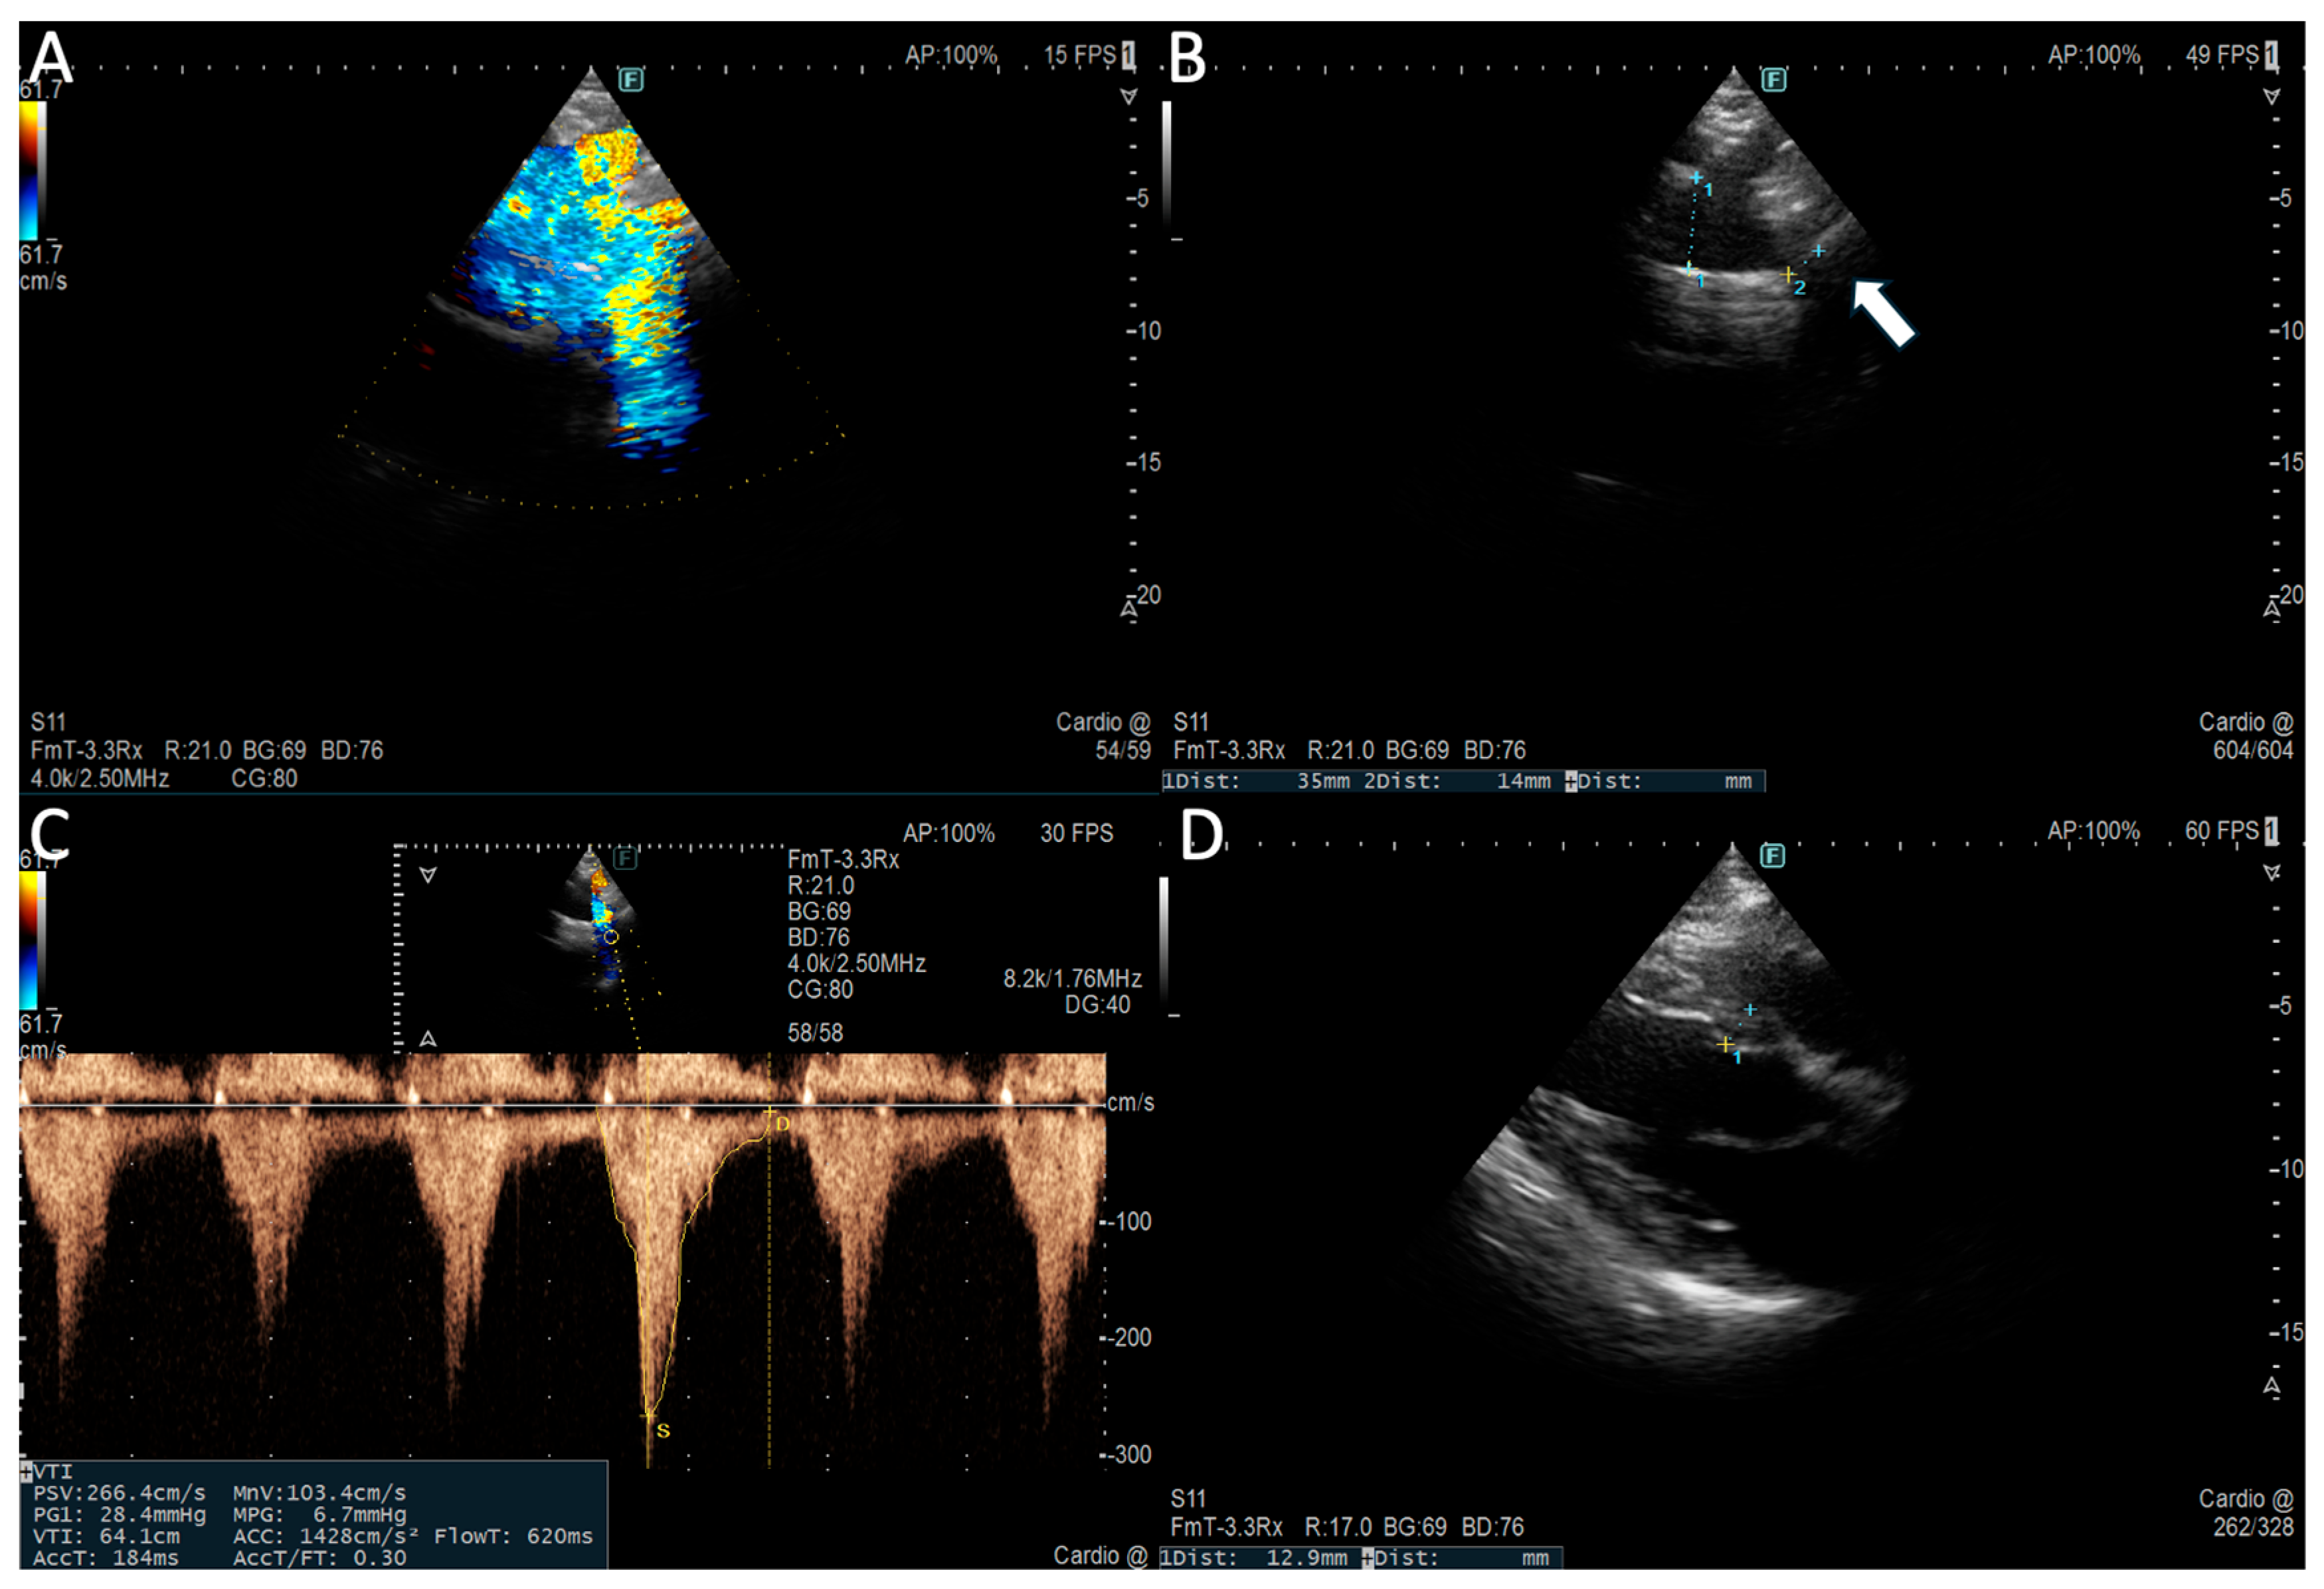

3.1. Comprehensive Anatomic Assessment and Clinical Implications

Additionally, the examination allows for the assessment of secondary cardiac changes. In the context of chronic pressure overload caused by CoA, the evaluation of left ventricular wall thickness and the presence of concentric hypertrophy are essential. While CMR is the gold standard for volumetric and functional quantification, ECG-gated CTA provides excellent morphological assessment of the ventricles. The detection of significant hypertrophy reinforces the diagnosis of a hemodynamically significant and long-standing coarctation, contributing to the overall risk stratification of the patient [5] (Figure 2).

Figure 2. Assessment of aortic coarctation by CT. A. CTA sagittal view of aortic coarctation; B. CTA 3D volume rendering reconstruction of aortic coarctation; C. CTA with detailed view of the bicuspid aortic valve in diastolic phase; D. CTA with reconstruction on ventricular short-axis view and measurement of ventricular walls in diastolic phase for assessment of LV hypertrophy.